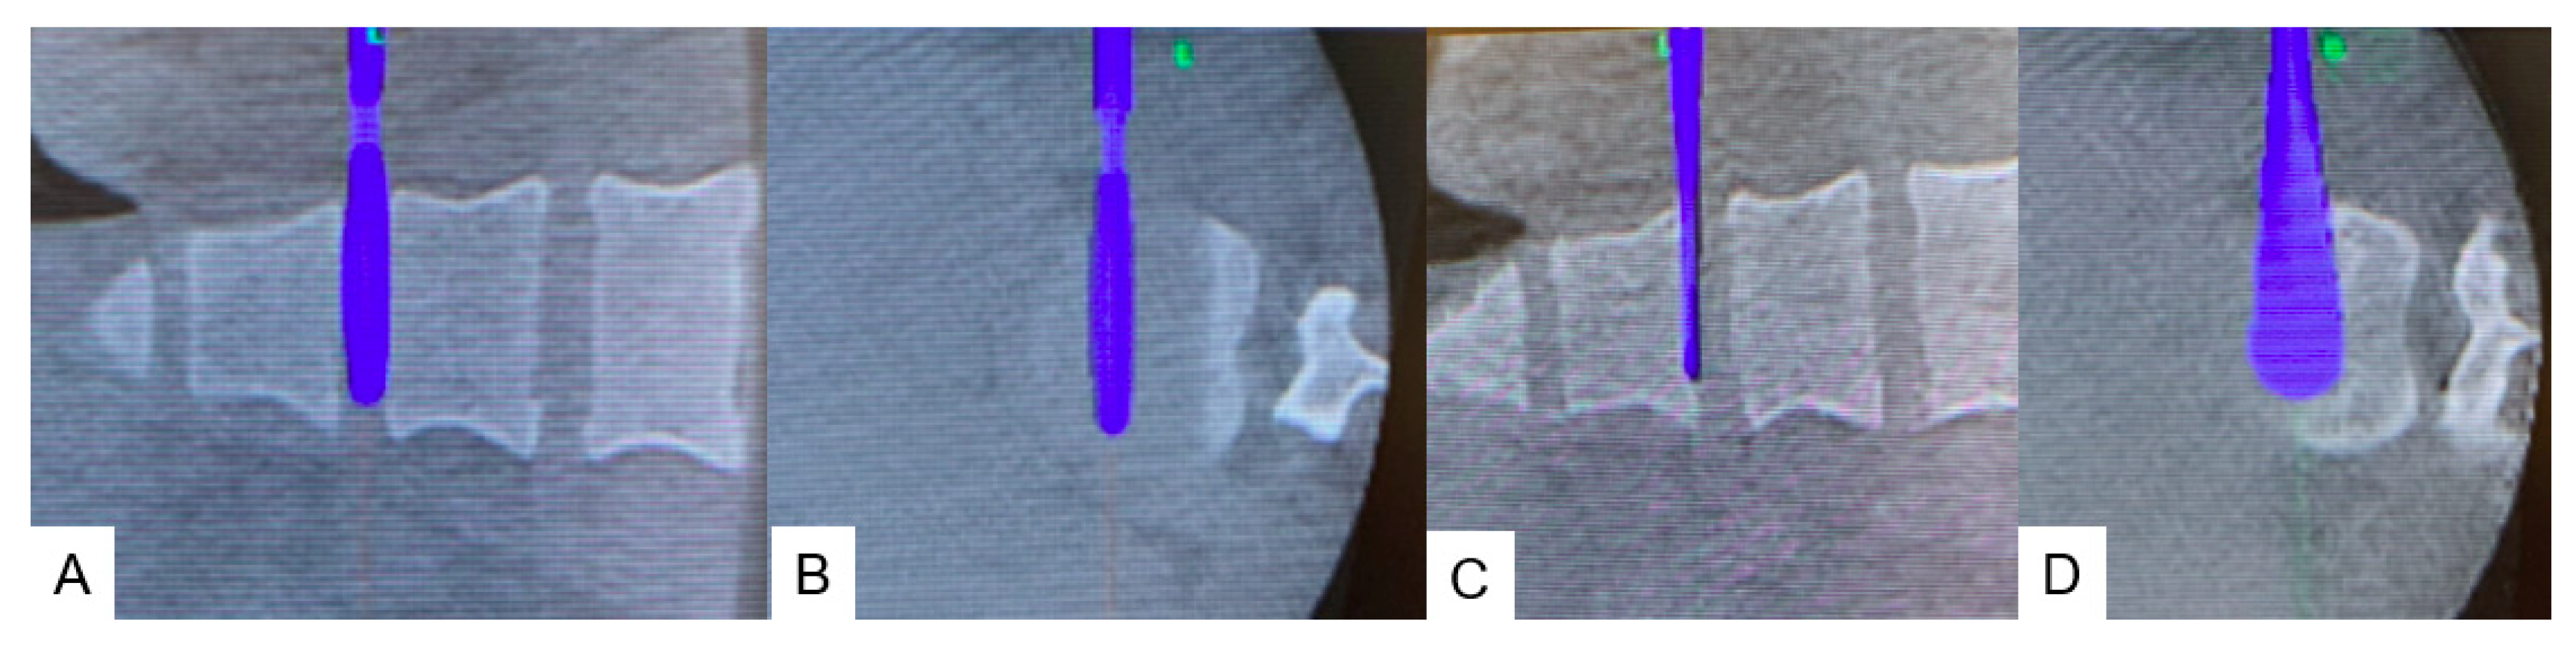

2.4.1. Anterior Discectomy

2.4.2. Posterior Osteotomy